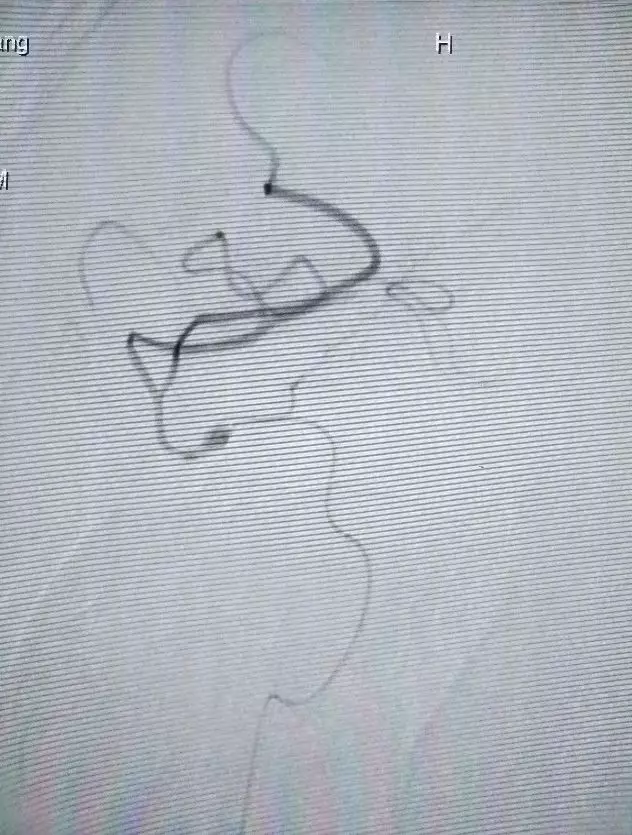

造影及诊断

诊断:

1、右侧大脑中动脉闭塞;

2、脑梗塞;

3、不完全性偏瘫。

治疗中造影(点击可查看大图)

微导管造影1

微导管造影2

微导管造影3

进行一次机械取栓

(Solitaire 4.0*20)

取栓后造影,发现为原位狭窄,调整为球囊扩张